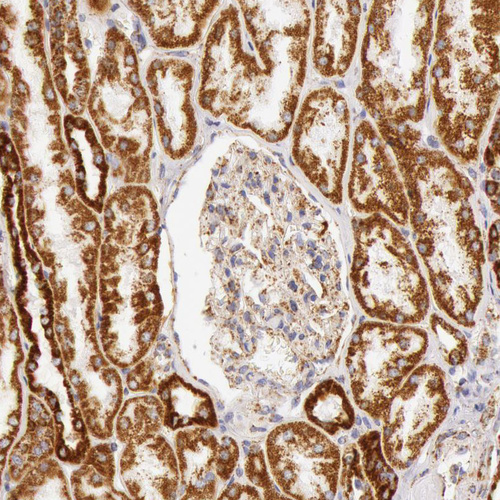

Immunohistochemical staining of human kidney, liver, prostate and small intestine using Anti-ATP5B antibody HPA001520 (A) shows similar protein distribution across tissues to independent antibody HPA001528 (B).